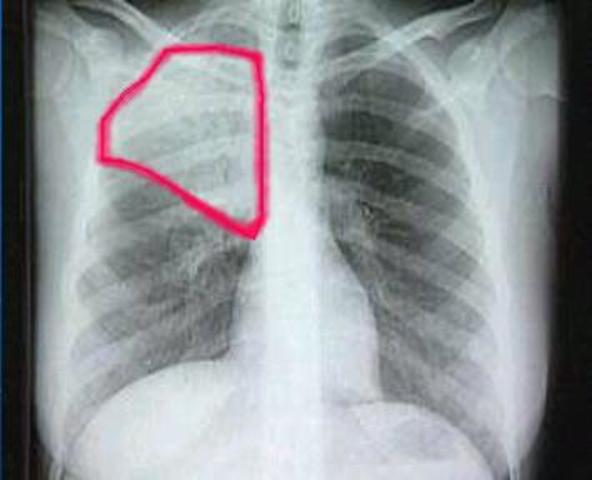

• Neumonía atípica

Neumonía atípica

Una nueva modalidad de neumonía atípica conocida como SRAG (Síndrome Respiratorio Agudo Grave) afectó a distintos países del mundo con 8.422 casos y 919 muertos en 2003, la mayor incidencia se produjo en China. Es causada por ciertas bacterias, a saber: Legionella pneumophila, Mycoplasma pneumoniae y Chlamydophila pneumoniae. Se denomina "atípica" porque los síntomas difieren de los de la neumonía debida a otras bacterias comunes